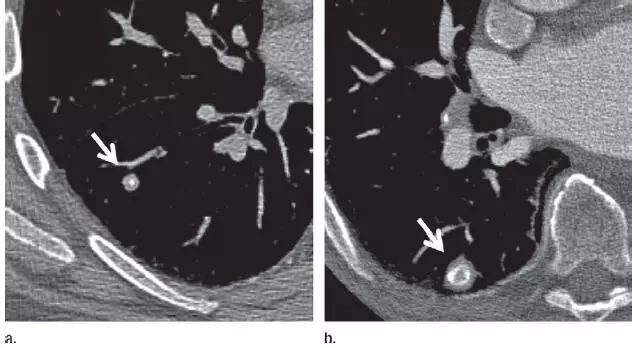

1、错构瘤

图 1 层厚 1 mm 的 CT 横断面图像,(a)为肺窗,(b)为软组织窗,显示边缘平滑、内含脂肪和钙化的实性结节(箭头),符合错构瘤表现。不建议进一步 CT 随访。